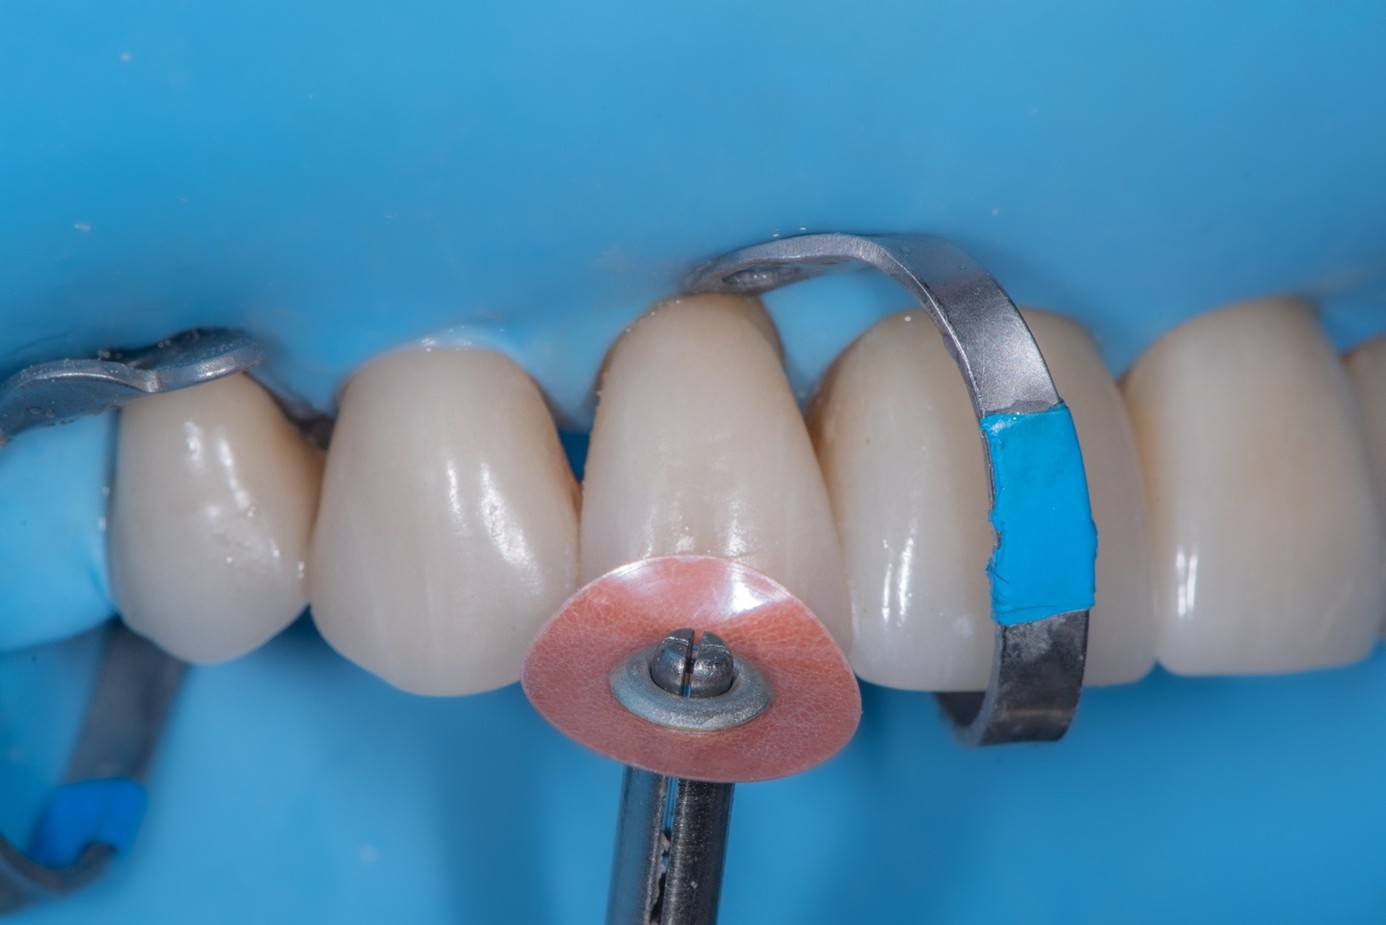

Intraorally, absolute rubber dam isolation was achieved to ensure a contamination-free environment (Figure 30). The prepared tooth was air-abraded with aluminum oxide to clean the surface and increase surface energy. A primer and bonding agent were applied to the tooth surface.

(30.) Intraoral view after absolute isolation with a rubber dam, showing the prepared tooth surface cleaned and roughened with sandblasting, ready for adhesive application and bonding to the crown.

Figure 30